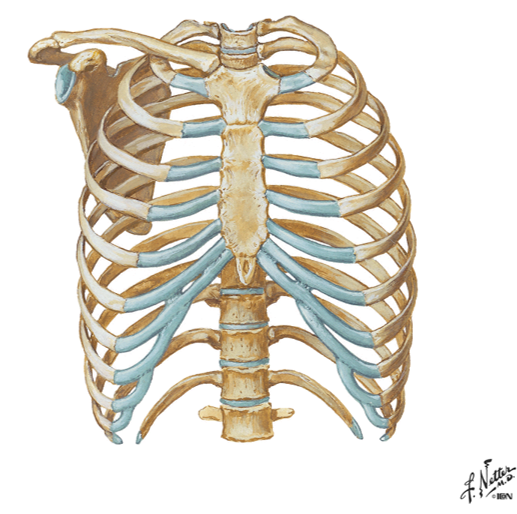

name the 3 bones of the thoracic wall?

their function?

- Bones of the thoracic wall = ribs, thoracic vertebrae and sternum

- Function – protect thoracic content…heart, lung, blood vessels, esophagus, etc…

identify the sub-divisions of the ribs (true, false and floating) and describe them?

- True (1-7) – attach “directly” to sternum

- False (8-10) – attach “indirectly” to sternum thru cartilage

- Floating (11-12) – do not attach to the sternum AKA dont even make their way around

describe typical vs. atypical ribs?

- Typical ribs = 3-9...have all the "usual" landmarks of the rib

- Atypical ribs = 1,2 10-12...dont have the typical landmarks that a rib would have